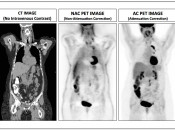

Three sets of images are produced for interpretation by the radiologist (addressed in greater in detail, here).

1. CT images (in three planes)

2. Non-Attenuation Corrected PET Images

3. Attenuation Corrected PET Images [Fig. 3]